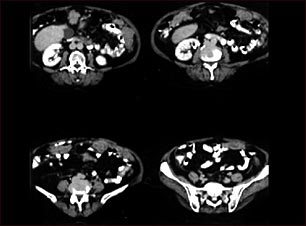

TC de cáncer peritoneal y de ovario

TC de la parte inferior del abdomen que muestra una metástasis del cáncer de los ovarios hacia el peritoneo.